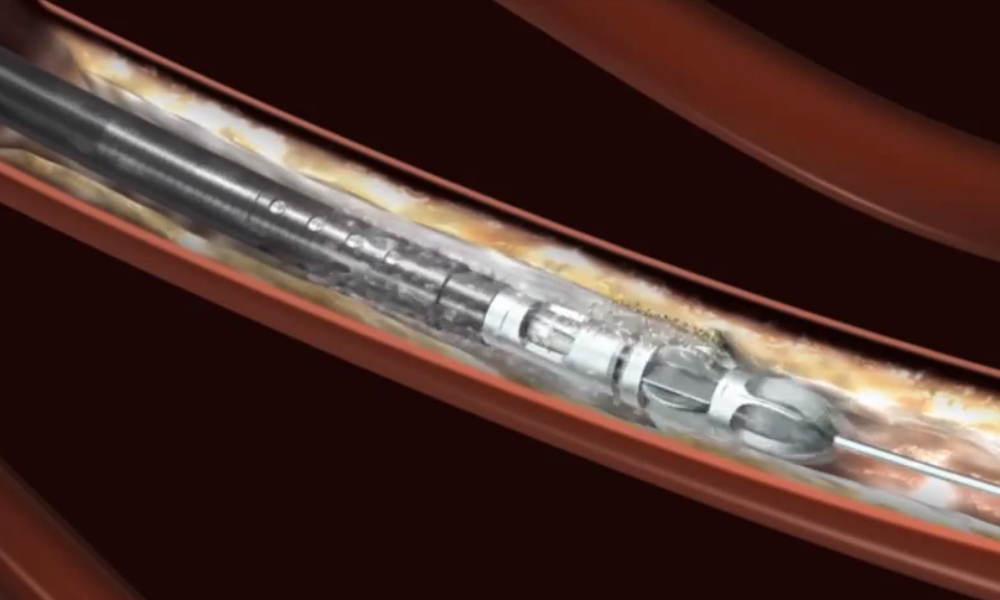

Product Information

Nov 03, 2015Jetstream Atherectomy System Selection Guide

Jetstream Catheter Selection Guide PDF, 418.0 KB